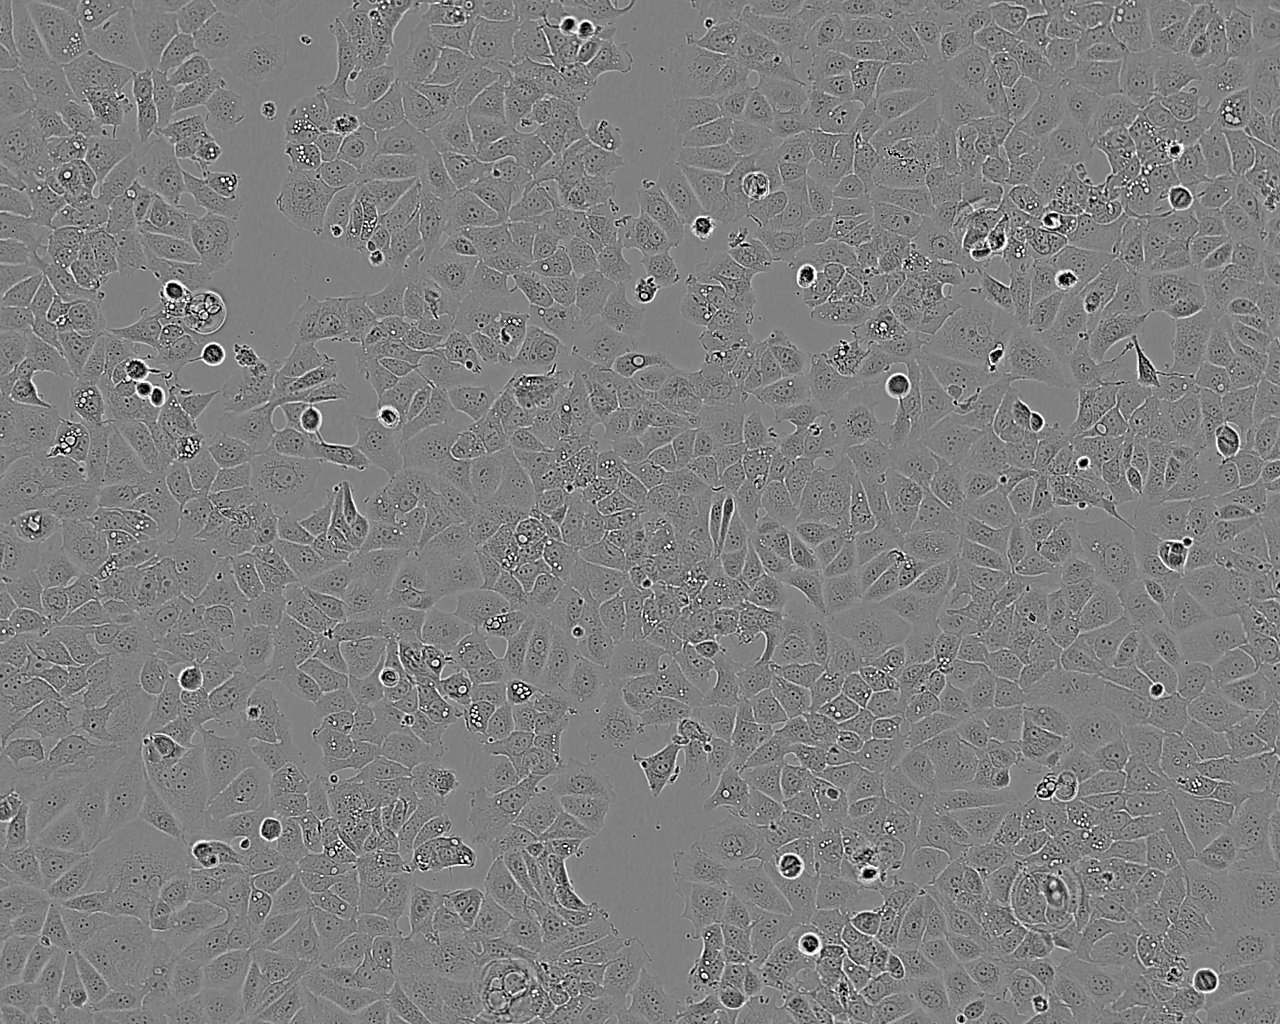

细胞形态:上皮细胞样

细胞生长:贴壁

细胞生长特性:贴壁生长